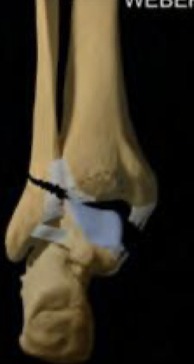

Weber C

Fx de peroné por encima del nivel del plafón tibial